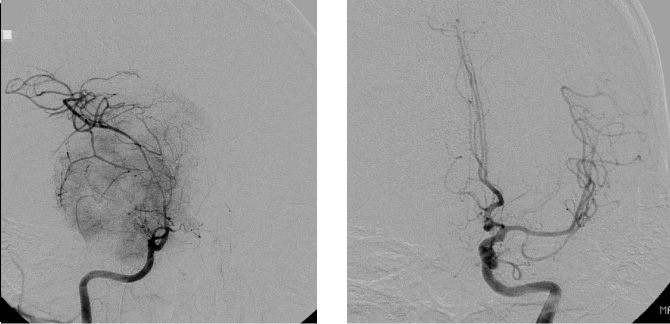

症例4

症例4は58歳。顔面の違和感で発見された小脳橋角部、テント髄膜腫である。三叉神経や外転神経、滑車神経などを巻き込む腫瘍。脳幹圧迫も強く症状は軽微であったが、腫瘍摘出を行った。後方複合錐体アプローチで一期的に神経を温存して腫瘍を摘出した。一時的に滑車神経麻痺による下方を見た時の副視が出現したが、改善している。

術前MRI 右側の脳神経を巻き込む腫瘍

神経を温存し腫瘍摘出